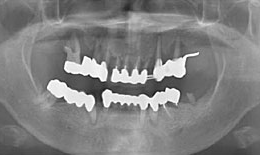

治療方法

上顎

保存困難な歯を抜歯後、インプラントを7本埋め込み、ボーンアンカードブリッジを装着した

下顎

保存困難な歯を抜歯後、インプラントを5本埋め込み、セラミックスクラウンを被せた